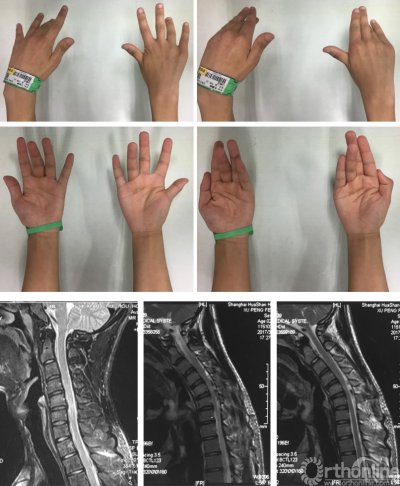

病例一:男,16岁,主诉:左手肌萎缩1年余,右手肌萎缩6月。

体检:双手肌肉萎缩、畸形、活动明显受限,手内肌肌力0-III级。

病例二:男,20岁,主诉:双手肌肉萎缩伴无力2年余。

体检:双手肌肉萎缩、双手指屈曲畸形,双腕背伸受限,远端肌力0-III级